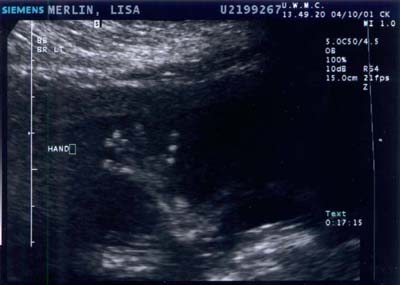

Baby B on 10 APRIL 2001 - Week 17

Baby B waving